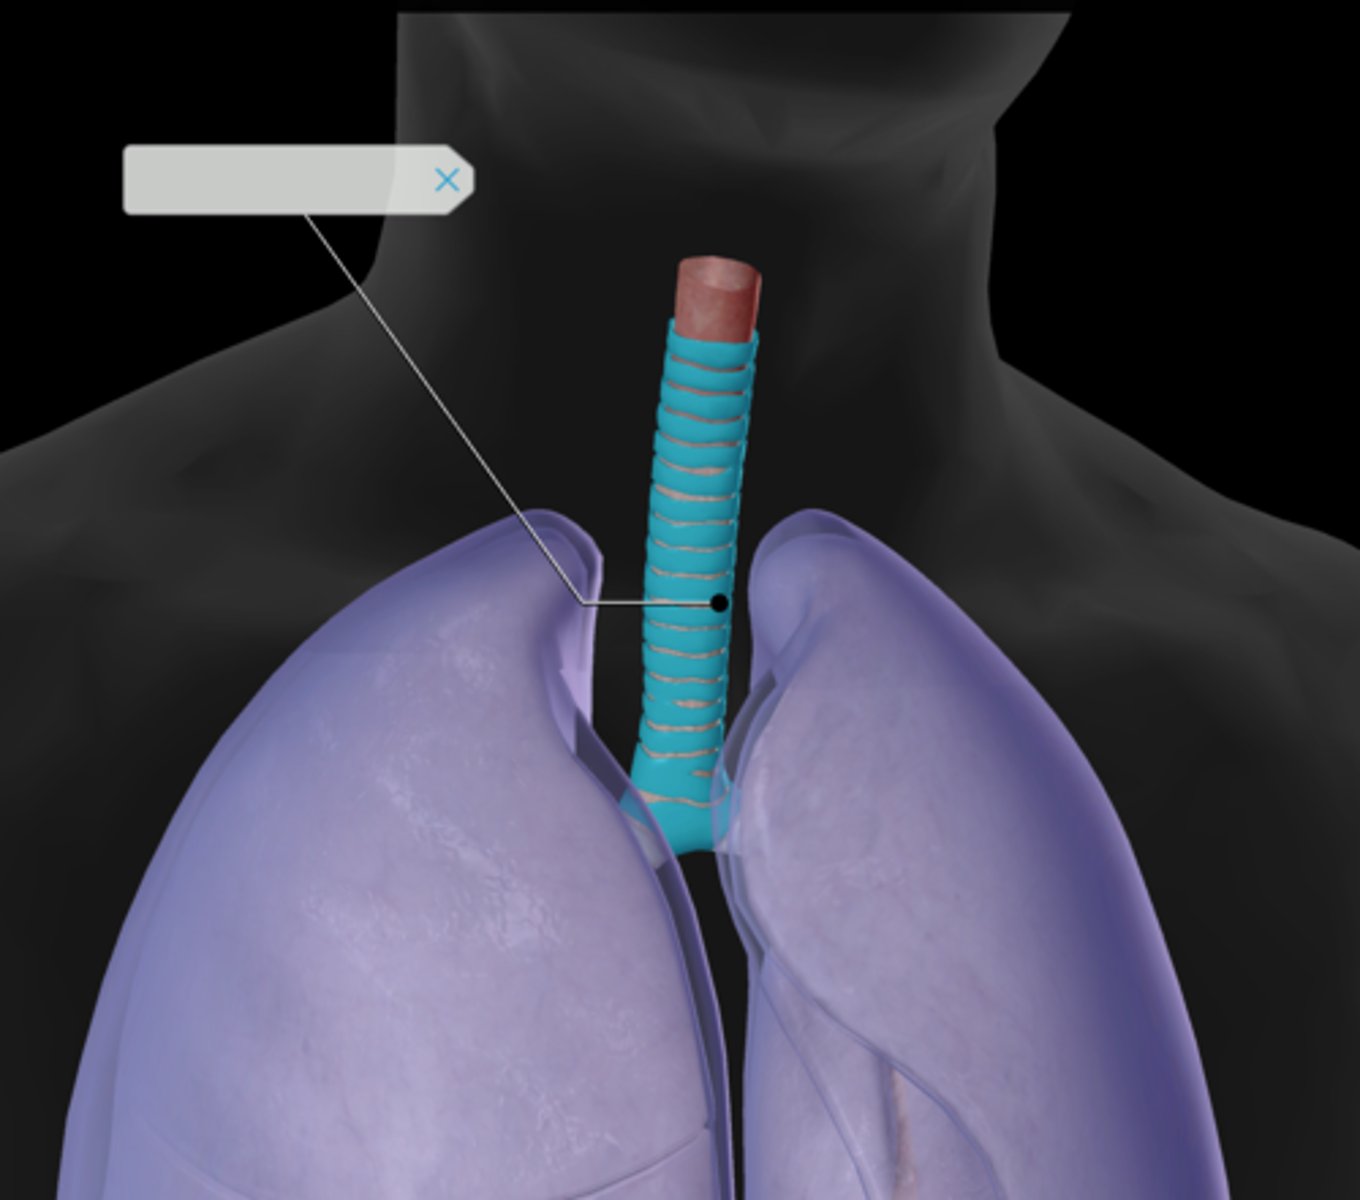

Trachea

Tracheal cartilaginous rings